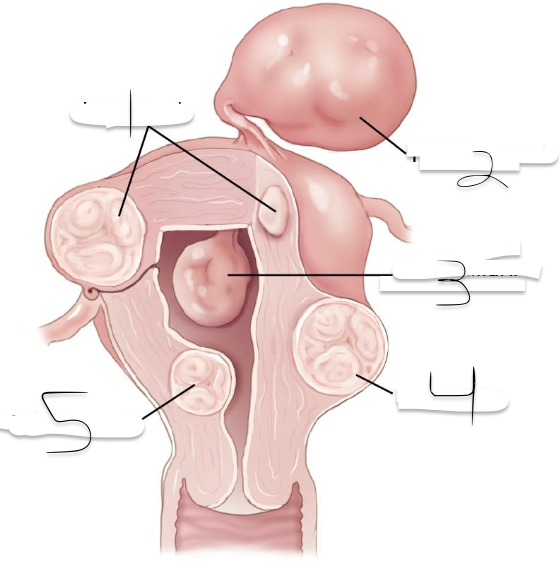

Leiomyomas can be_______________________?

Submucosal, Intramural, Subserosal

(displacing or distorting endometrial cavity with subsequent irregular or heavy menstrual bleeding, Infertility)

What kind of Leioyomas can this be?

Submocosal

(confined to myometrium; most common type): may enlarge to cause pressure on adjacent organs; Infertility or recurrent pregnancy loss.

What kind of Leioyomas can this be?

Intramural

(projecting from the peritoneal surface of uterus): Can become pedunculated and appear as extrauterine masses, may enlarge to cause pressure on adjacent organs

What kind of Leioyomas can this be?

Subserosal

1?

Intramural

2?

Pedunculated

3?

Intracavitary

4?

Suberous

5?

Submuscosal